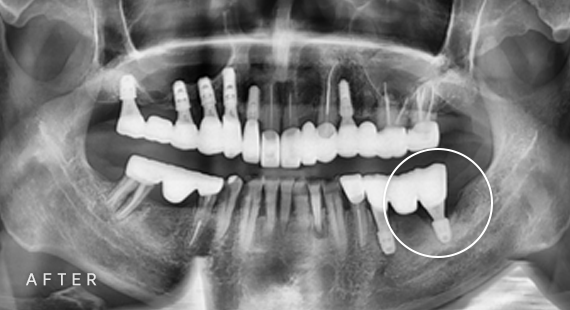

임플란트